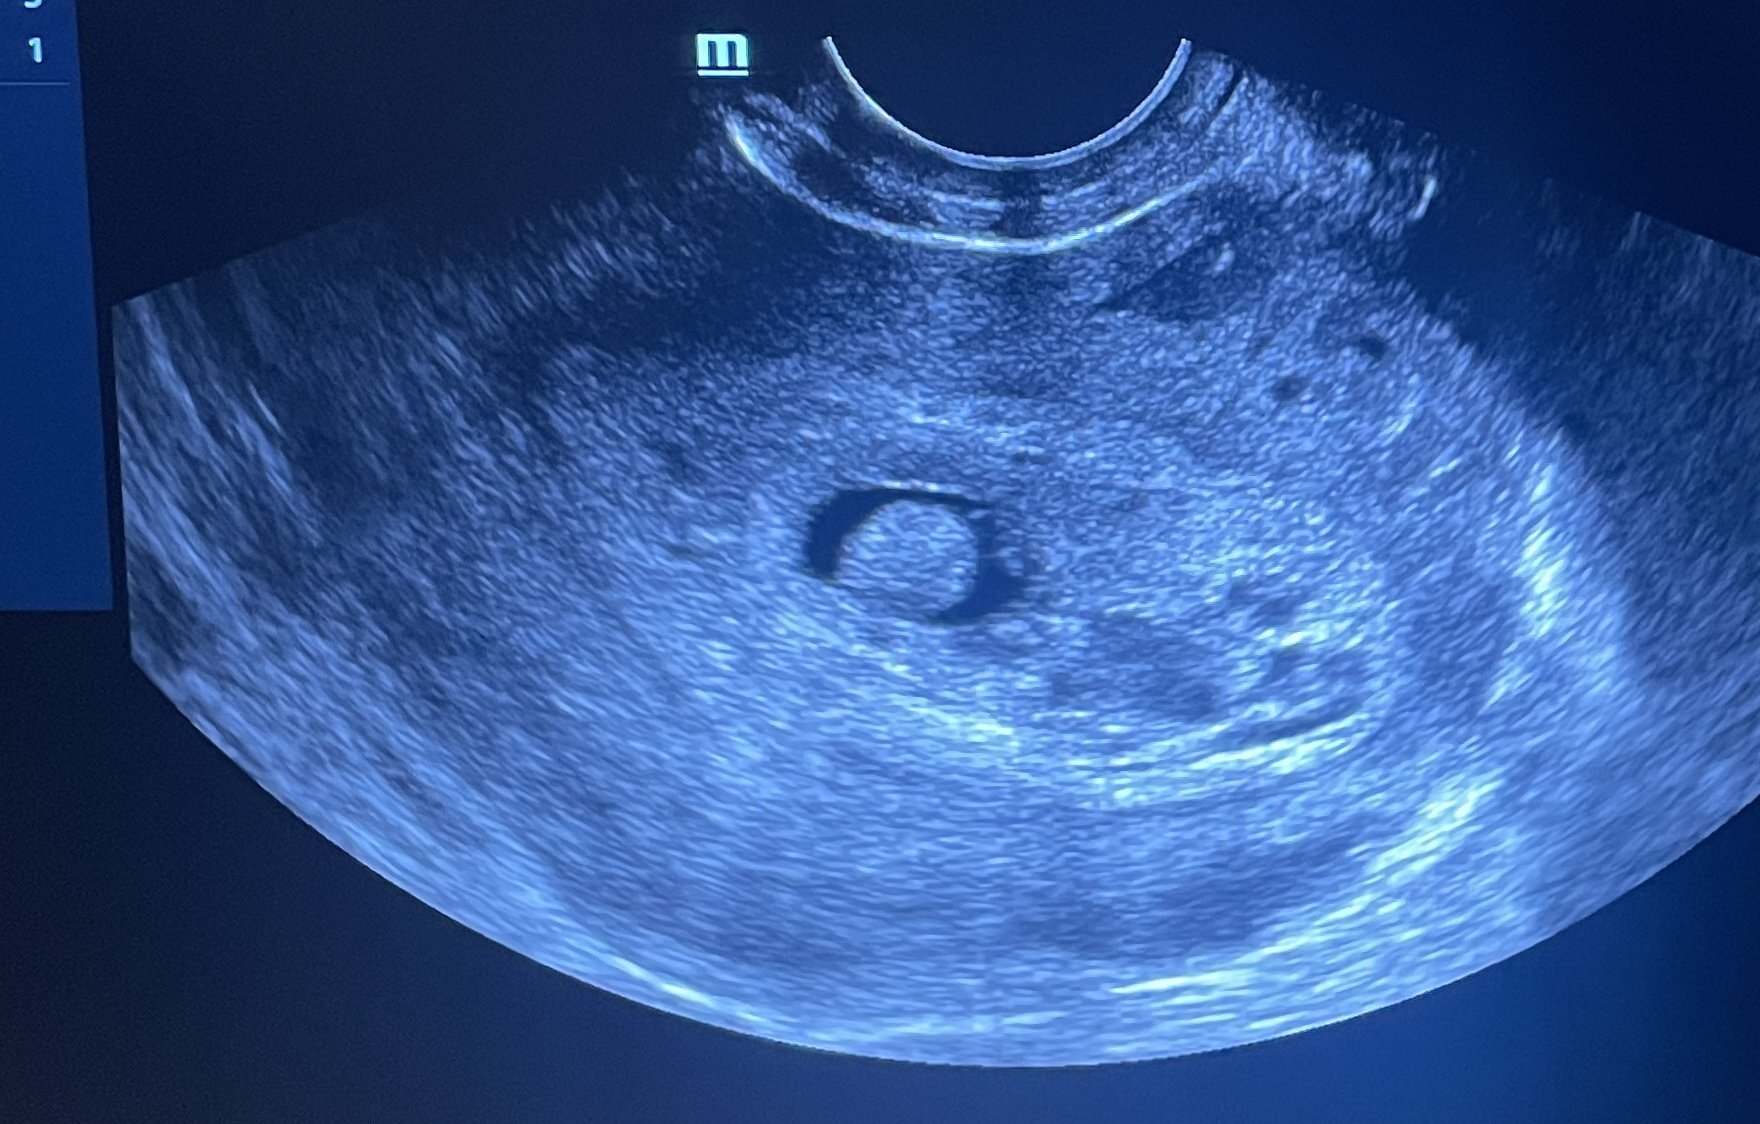

Какво представлява изображението от ехографията на 5-седмична и 2-дневна бременност?

Дали някой е минал през това и така ли изглежда в тези ранни седмици? Тя беше доста объркана, затова се допитвам тук…